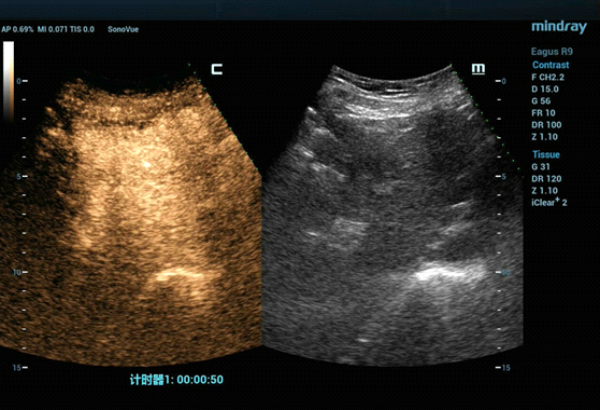

W konwencjonalnym obrazowaniu USG w skali szaro?ci nie uda?o si? uwidoczni? guza w segmencie IV zaobserwowanego w badaniu TK jamy brzusznej. W badaniu USG z kontrastem (contrast-enhanced ultrasound, CEUS) zmiana wykazywa?a wzmo?one unaczynienie w fazie t?tniczej (Obraz 2.) z izointensywnym wzmocnieniem w fazach wrotnej i pó?nej (Obraz 3.)./p>

Guz by? izoechogeniczny i nie mo?na by?o wyra?nie uwidoczni? go w badaniu USG 2D w skali szaro?ci, zatem konwencjonalna kontrola wy??cznie z zastosowaniem USG mog?a skutkowa? niedok?adnym pozycjonowaniem i niepe?n? ablacj?. Z kolei obrazowanie z wykorzystaniem fuzji obrazów uzyskanych w badaniu USG w czasie rzeczywistym z danymi uzyskanymi w badaniu TK z kontrastem umo?liwi?o dok?adne pozycjonowanie elektrody i skuteczne leczenie zmiany metod? przezskórnej MWA. Przed zabiegiem przeprowadzono badania CEUS w celu potwierdzenia umiejscowienia guza oraz po zabiegu w celu oceny obszaru poddanego ablacji i potwierdzenia skuteczno?ci leczenia.

Zastosowanie badania CEUS w po??czeniu z fuzj? obraz√≥w umo?liwia precyzyjne zlokalizowanie zmiany ogniskowej w w?trobie, dok?adne umiejscowienie elektrody mikrofalowej oraz monitorowanie i ocen? obszaru poddawanego ablacji вАУ a to wszystko w czasie rzeczywistym. Zabieg MWA pod kontrol? USG z wykorzystaniem tych dodatkowych funkcji jest bezpieczny, mo?liwy do przeprowadzenia i odpowiedni do stosowania w warunkach klinicznych.